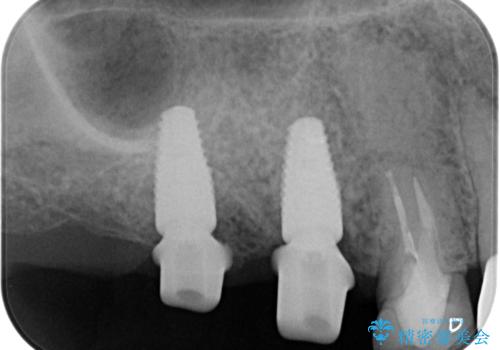

人工歯根であるインプラントを埋入することで奥歯でまたしっかりと噛める咬合機能を回復します。

- 88万円(インプラント×2・仮歯×2・チタンカスタムアバットメント×2・ジルコニアクラウン×2)費用は治療当時の料金となります